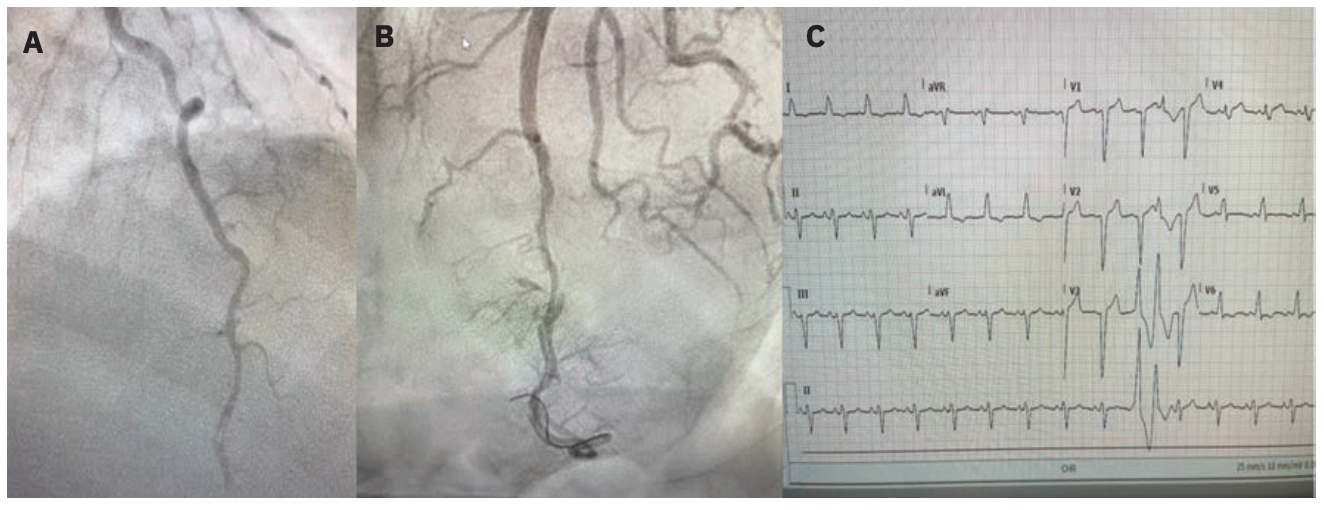

Takotsubo cardiomyopathy (TCM), also known as takotsubo syndrome, stress-induced cardiomyopathy, transient apical ballooning, or broken heart syndrome, is a condition that is generally triggered by emotional or physical stress, and is characterized by transient regional left ventricular systolic dysfunction.36,37 Symptoms of TCM are often similar to ACS prior to clinical assessment and imaging, and may present as an apical, anterior STEMI or non STEMI. The onset of symptoms in most TCM cases is usually preceded by an identifiable acute emotional or physical stressor, or a combination of both.29 In the International Takotsubo Registry study, 36% of patients had experienced a physical trigger, 28% reported an emotional trigger, and 8% experienced both.35,36 It is estimated that >90% of TCM occurs in women.37,38 Fortunately, TCM will usually resolve within several months without complications and rarely causes other cardiovascular events.

In Figure 3, a 70-year-old woman, whose spouse had recently died presented with signs and electrocardiographic presentation of an anterior wall MI. Angiography revealed no obstructive coronary disease. Left ventriculography revealed a classic apical ballooning pattern associated with TCM. The patient was treated with medications and followed up with serial echocardiography. In less than 2 months, her left ventricular function had returned to normal.